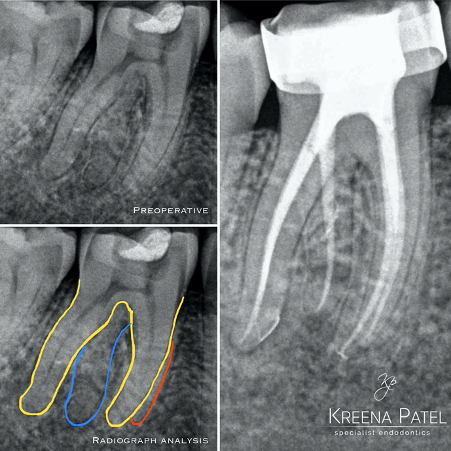

Radiographs and CBCT

It is important to assess radiographs carefully for the presence of extra roots.

In radix entomolaris, the disto-lingual root often lies on the same bucco-lingual plane as the main distal root.

This superimposition can ‘hide’ the root, making it difficult to identify. Therefore, a parallax radiograph (taken from a 30 degree mesial or distal angulation) is helpful.

Three-dimensional imaging using CBCT is also very useful in identifying an additional root and treatment planning. It provides a ‘roadmap’ for endodontic treatment and highlights any curvatures present (Figure 5).

In a radix entomolaris, the main distal root (DB) may still have two canals (DB1 & DB2) (Figure 5). The DB2 is more difficult to locate and can be hidden in the isthmus between DB1 and DL. It is often in close proximity to DB1.